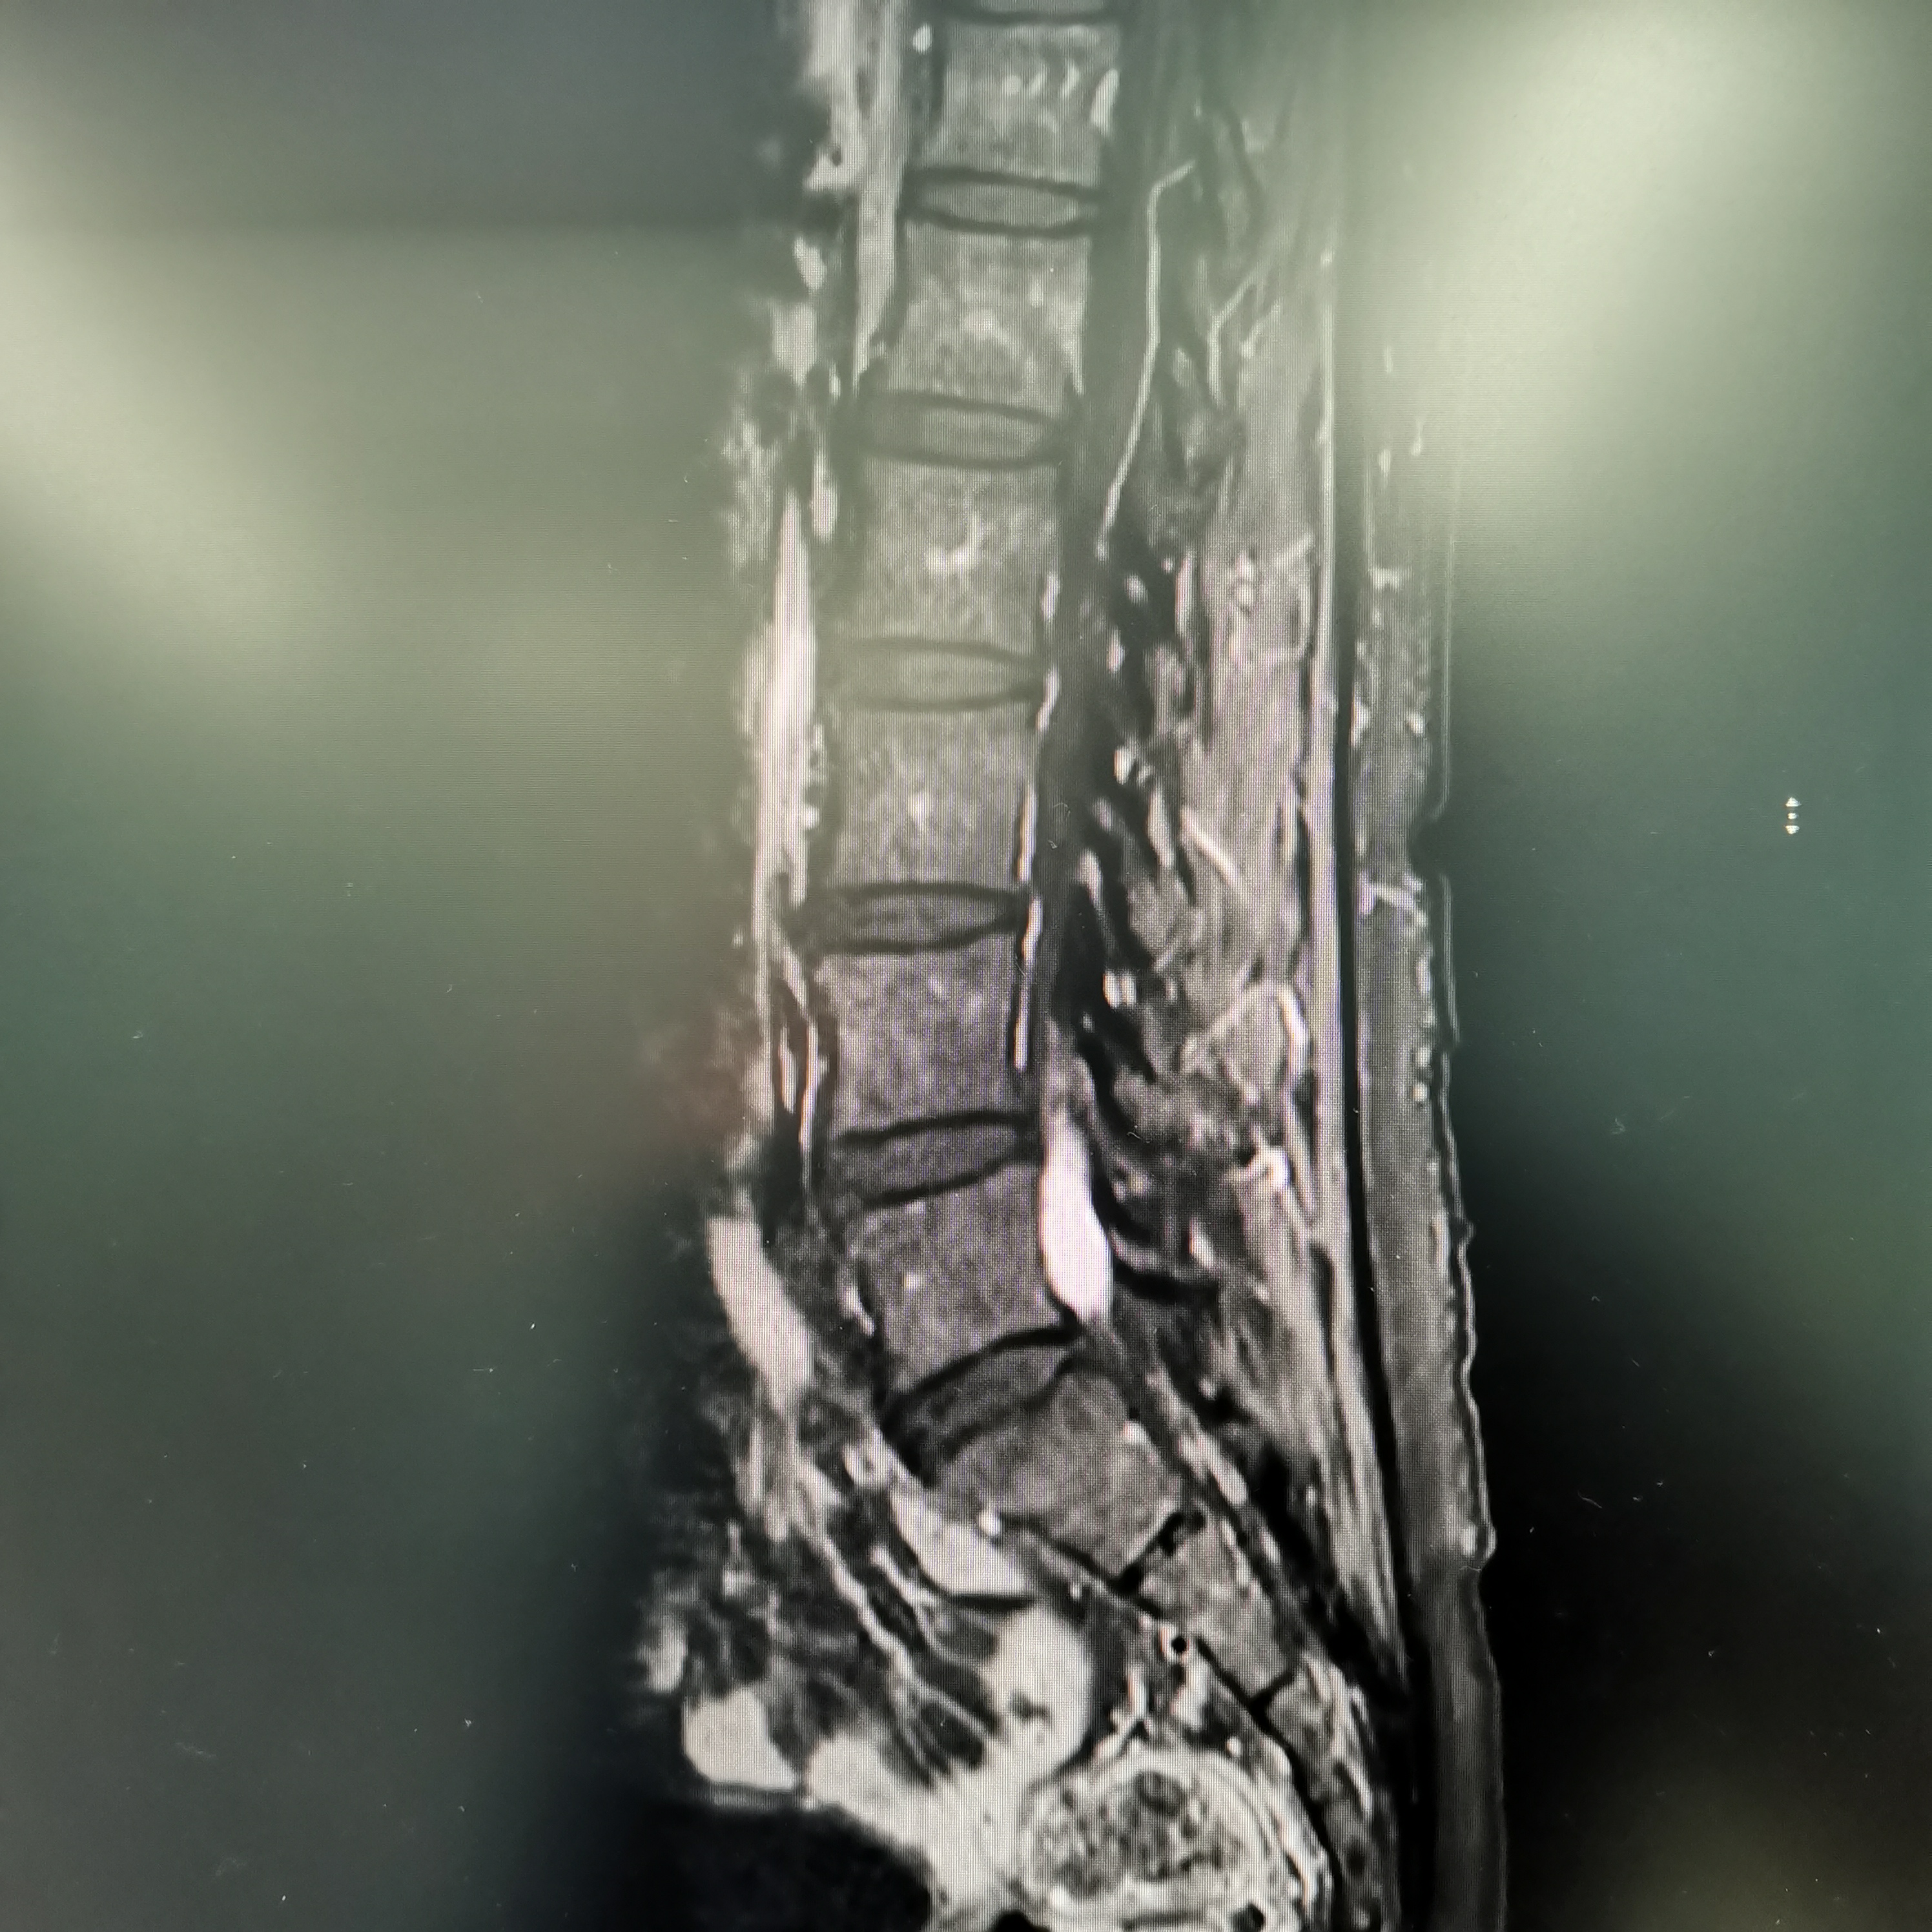

膝关节疼痛,原因是椎管内肿瘤,哑铃型生长,全切肿瘤,保留神经,疼痛症状消失…